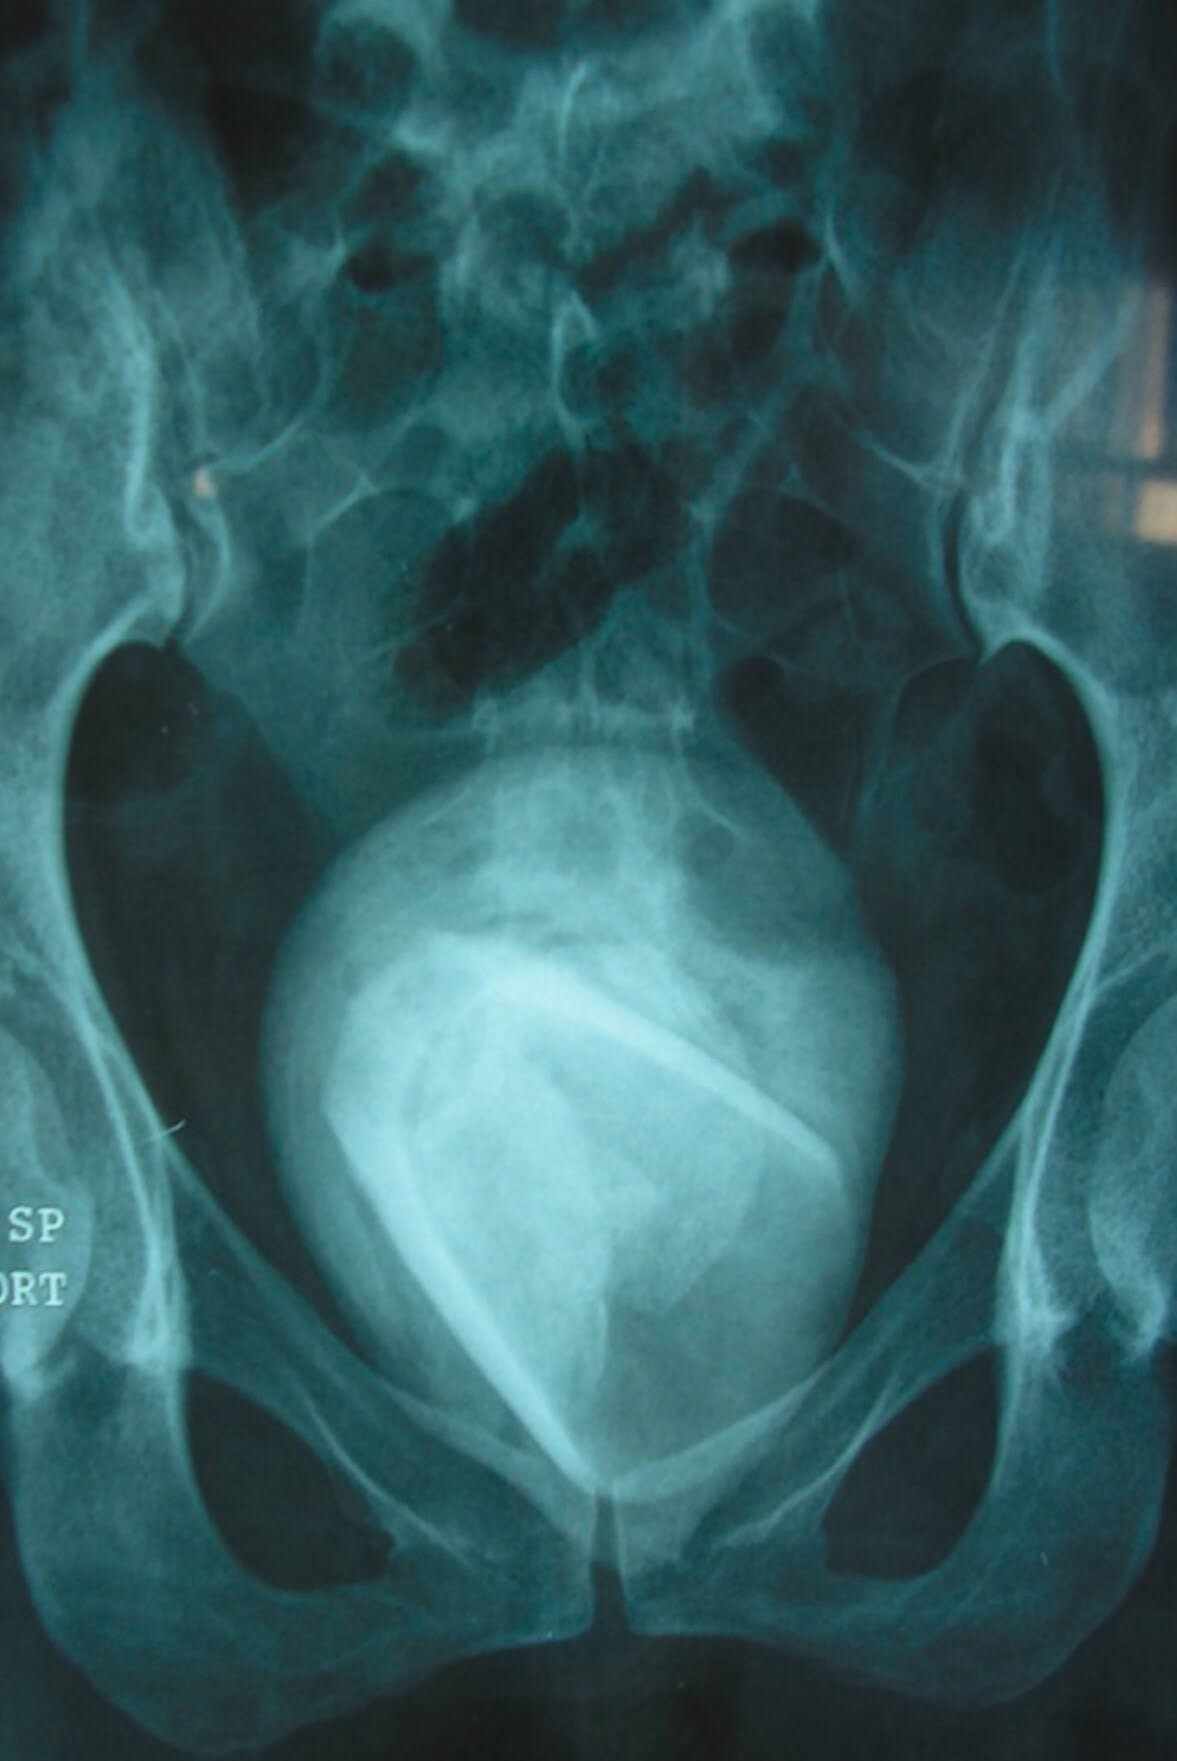

チュニジアにて驚愕のニュース。マンコじゃなく、尿道に ”ガラスのコップ” を挿入しオナニーしていた女性。それは取り出す事ができなくなりそのまま放置… その4年後、尿路感染症の症状で病院を訪れた女性を医師がレントゲン撮影した結果、膀胱結石で覆われたガラスのコップを発見、摘出したとの事。画像2枚。(※ TOP画はイメージ)

※ 医師も驚愕… レントゲン撮影で発見された、女性の体内にあるガラスのコップ

※ 手術により摘出された、膀胱結石で覆われたガラスのコップ